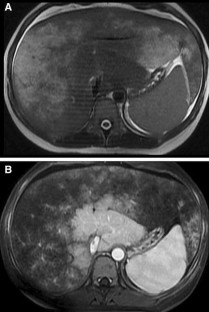

Fig. 3